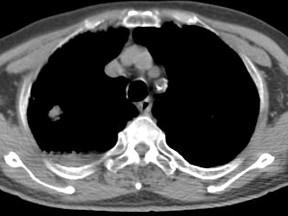

问题 男,76岁,气喘数年,胸痛一月余,结合影像图像,选择最可能的诊断 ( )

选项 A、右上肺错构瘤 B、右上肺肉瘤 C、肺间质纤维化 D、右上肺瘢痕癌 E、右上肺结核球

答案 D